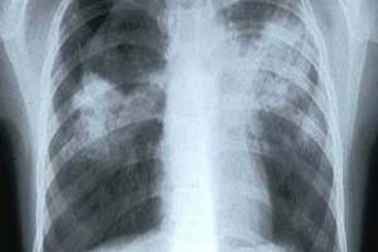

Gần 40% bệnh nhân lao trong cộng đồng chưa được phát hiệnTình hình dịch tễ bệnh lao tại Việt Nam còn rất nặng nề, tốc độ giảm quá chậm. WHO ước tính mỗi năm Việt Nam có khoảng 13.000 người tử vong do lao, cao hơn số người tử vong vì tai nạn giao thông.

Việt Nam trong top những nước có nhiều bệnh nhân lao mớiTại lễ mít-tinh hưởng ứng Ngày chống lao thế giới (24/3) tại Hà Nội, đại diện Bộ Y tế cho biết, hiện Việt Nam hiện đang ở vị trí thứ 12 trong số 22 nước có số bệnh nhân lao mới mắc hàng năm cao nhất thế giới, với khoảng 44% dân số nhiễm lao.